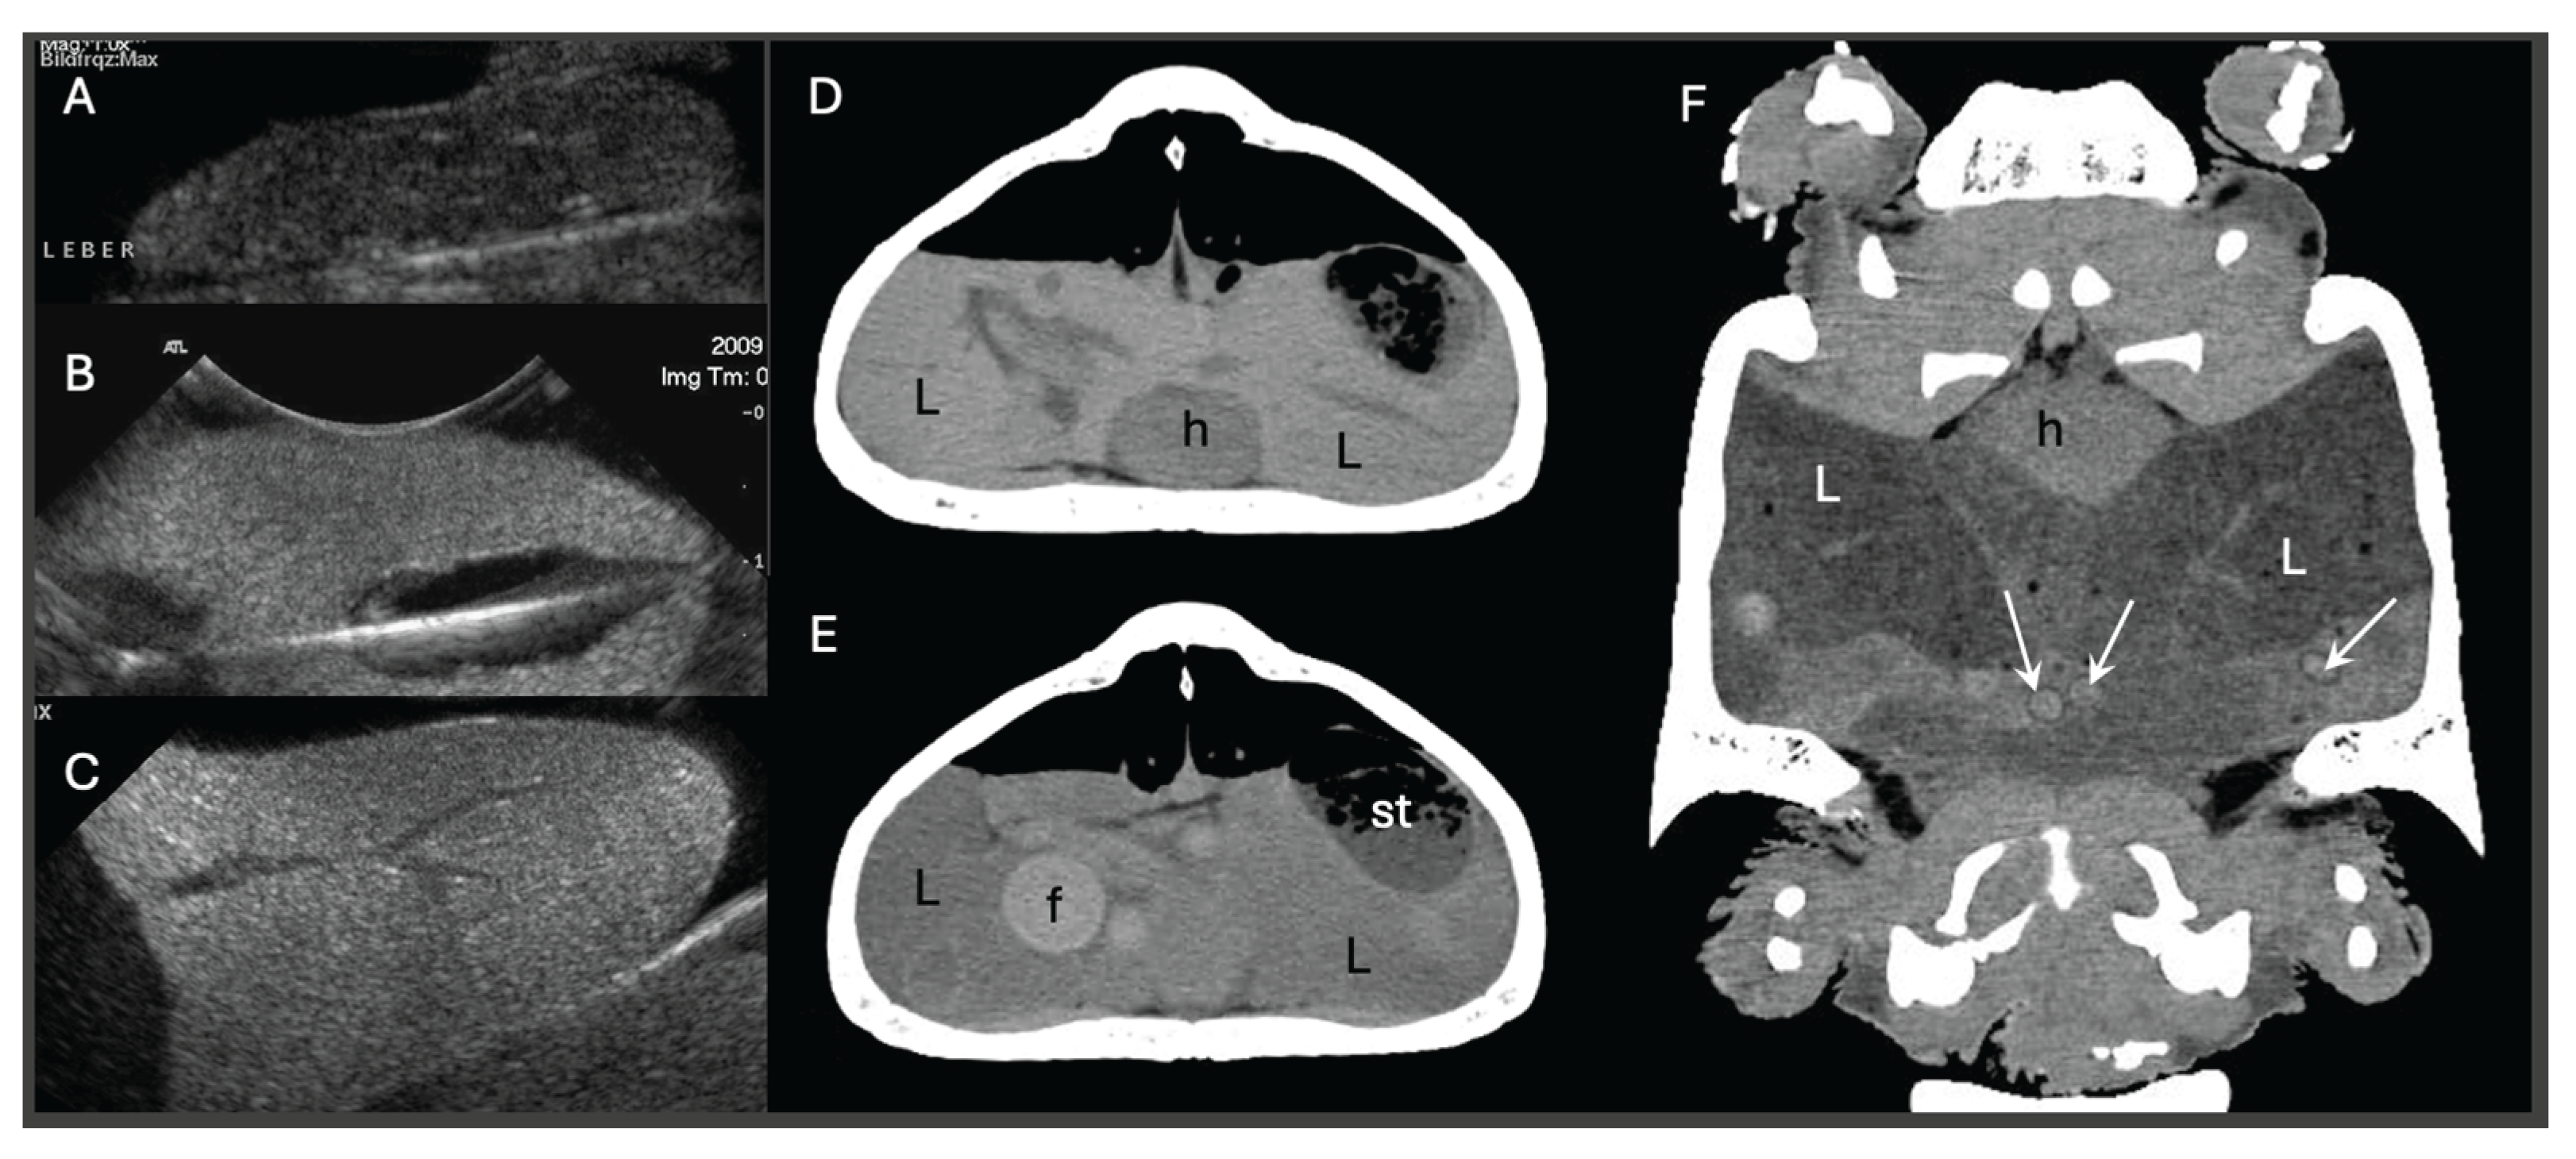

- Gumpenberger, M. Diagnostic imaging of reproductive tract disorders in reptiles. Vet. Clin. N. Am. Exot. Anim. Pract. 2017, 20(2), 327–343. [Google Scholar] [CrossRef]